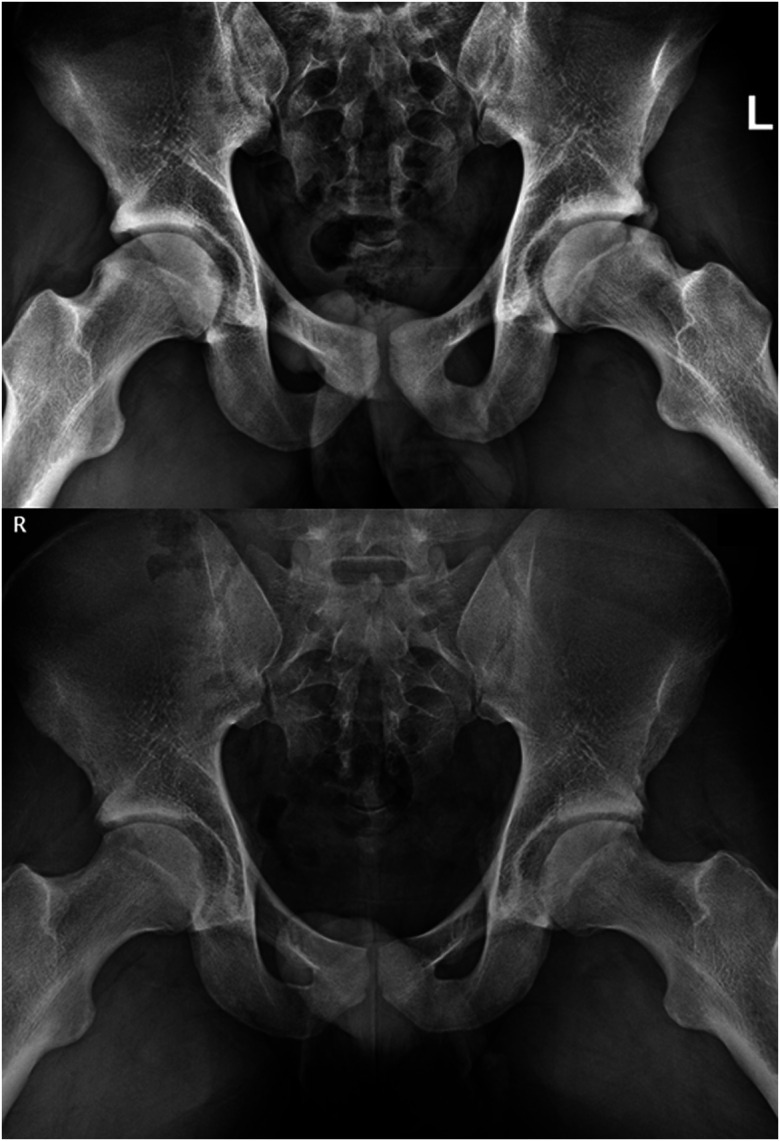

» Femoroacetabular impingement (FAI) is the premature contact of the femoral head-neck junction with the superior acetabular rim during hip range of motion, which may further damage intra-articular soft tissue structures and lead to the accelerated development of osteoarthritis.» FAI syndrome is diagnosed by a triad of symptoms, clinical signs, and imaging findings, and is a common cause of hip pain in young patients that have a significant impact on patient hip-related function and quality of life.» The treatment of FAI syndrome begins with noninvasive nonoperative modalities such as patient education and supervised exercise-based physical therapy. For recalcitrant symptoms, various injections have been explored for both diagnostic and therapeutic purposes; however, the efficacy of these interventions have generally not been demonstrated outside of the short term» In this article, we examine the available literature regarding the nonoperative treatment of FAI and provide insight into the effectiveness of current treatment modalities.